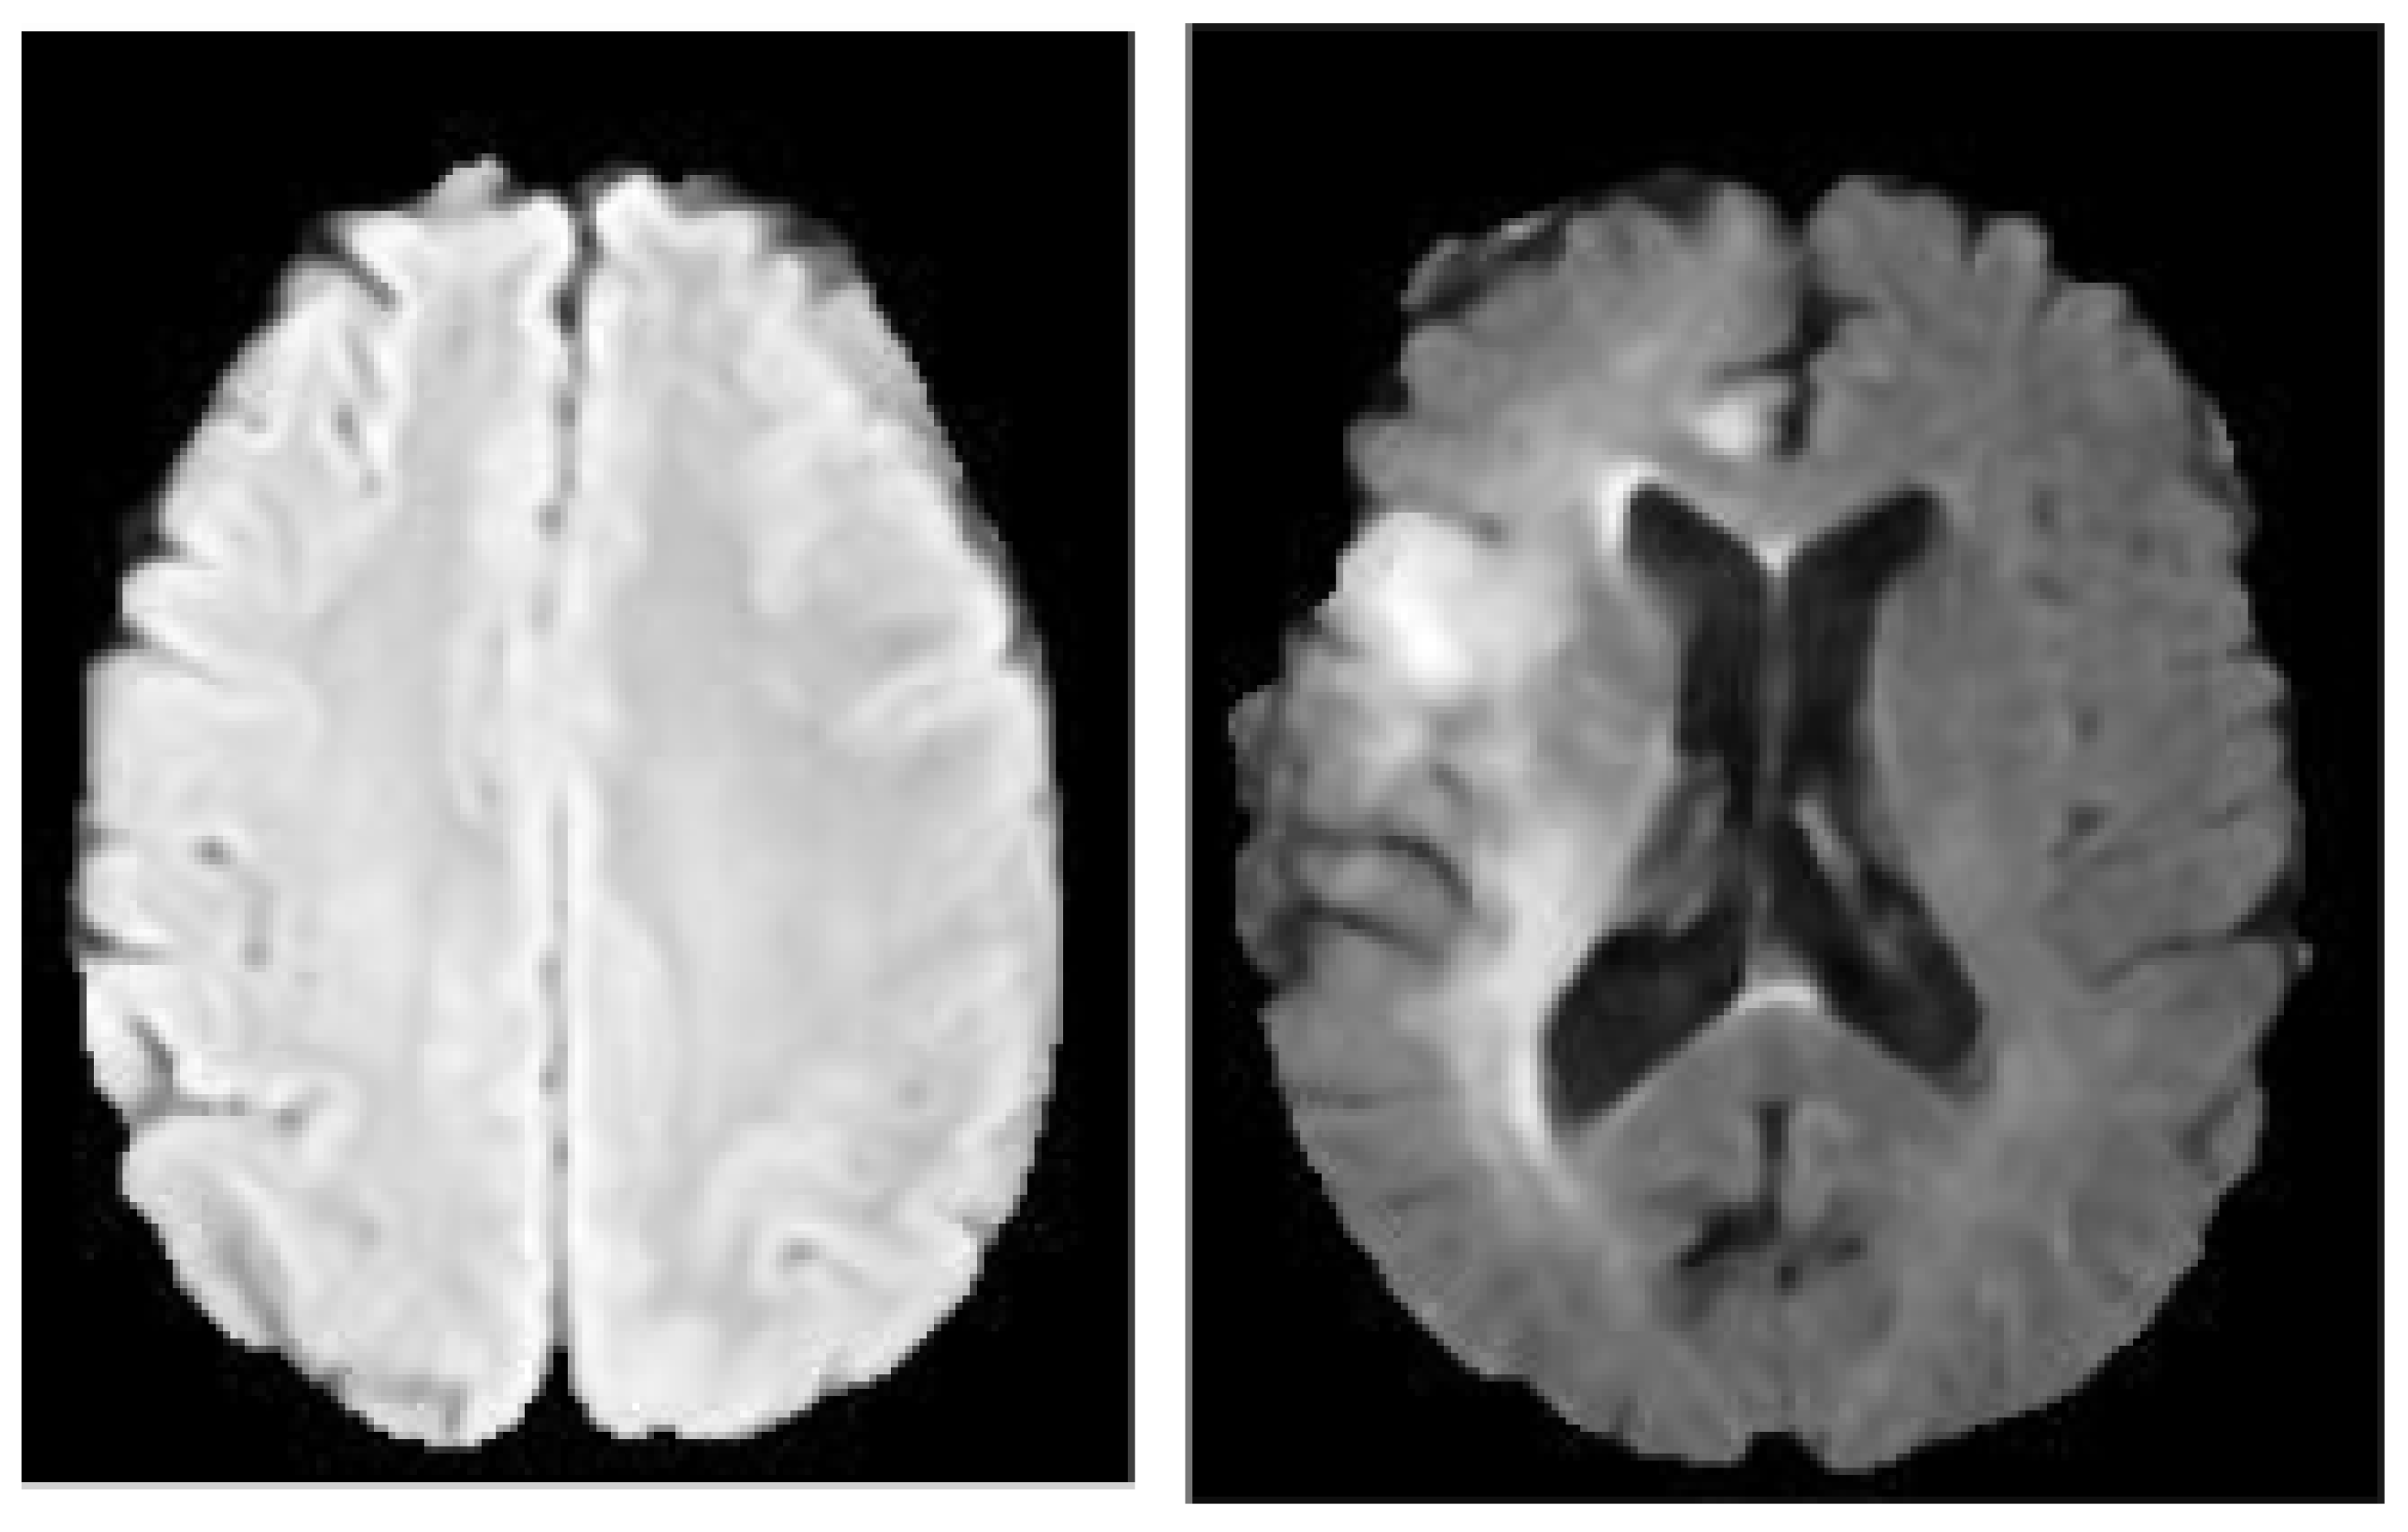

CLAHE Images

This study utilized CLAHE as a pre-processing technique to enhance the contrast and features of the image by pronouncing abnormal patterns in the image. Contrast Limited Adaptive Histogram Equalization (CLAHE) algorithm produces a more realistic appearance among the histogram equalization family and it is capable of reducing noise amplification. We have examined the efficacy of CLAHE algorithm and adopted it to the MRI dataset, as shown in Figure 2.

Figure 2. CLAHE Pre-processing. The images on the left are the raw images while the images on the right are the processed images.